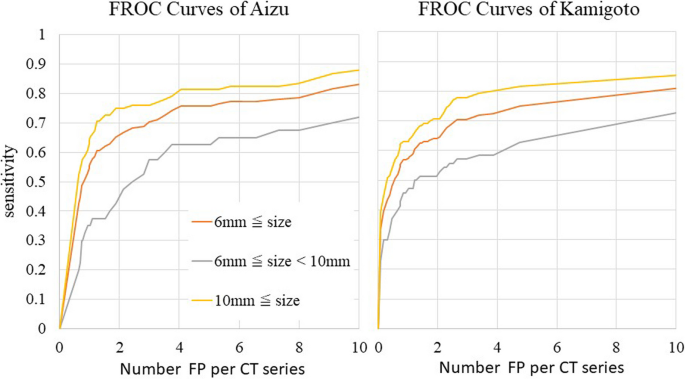

Fig. 7 shows FROC curves for the CT images of the Aizu and Kamigoto datasets. The sensitivities for lesions ≥6 mm and lesions ≥10 mm when four FP lesions were allowed were 0.755 and 0.810 with the Aizu dataset and 0.729 and 0.802 with the Kamigoto dataset, respectively. It was also confirmed that the sensitivity increased when the allowed number of FP lesions was increased. However, the sensitivities for lesions 6 to 10 mm were 0.625 and 0.593 when four FP lesions were allowed and 0.675 and 0.689 when eight FP lesions were allowed, respectively; these values were considered low.

Sensitivities of the external validation dataset per CT series by FROC analysis. Sensitivity was evaluated in each supine or prone position.